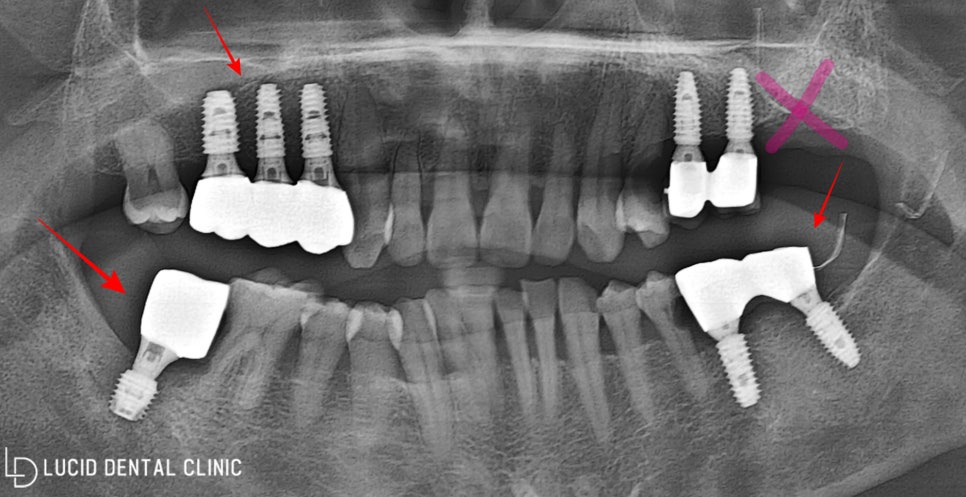

- 임플란트 수술 종료

픽스처 식립 후 약 4개월이 지나자

무사히 회복한 모습을 보이셨는데요

바로 제작한 최종 보철을 체결하며

계획한 치료 과정을 모두 종료했습니다.

종료 후 촬영한 파노라마

엑스레이 사진이에요 ㅎㅎ

치아가 없어 제대로 된

식사조차 어려웠으나

이제 튼튼한 저작 기능을

사용할 수 있게 되었다며

크게 기뻐하셨는데요